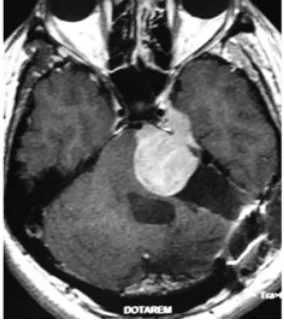

随后,患者再度出现面部麻木感与共济失调症状。此次磁共振检查结果令人警惕:肿瘤体积出现了显著扩大。临床团队判断肿瘤的生物学行为已发生根本性改变,遂实施根治性切除手术。

术后病理报告带来了最坏的消息:肿瘤已转化为恶性外周神经鞘膜瘤。免疫组化染色结果显示,此前在肿瘤细胞中呈弥漫阳性分布的S100蛋白,此时已变为仅灶性阳性,提示肿瘤细胞正在经历去分化过程。

然而恶化的速度远超预期。根治性切除手术后不过三个月,肿瘤即以极强的侵袭性迅速复发,并对脑干造成严重压迫。为维系基本生命功能,患者紧急接受了第二次手术以实施脑干减压。这一次的病理结果表明,肿瘤已进一步去分化,转化为间变性软组织肉瘤,神经源性标记物S100蛋白的表达已完全丧失。